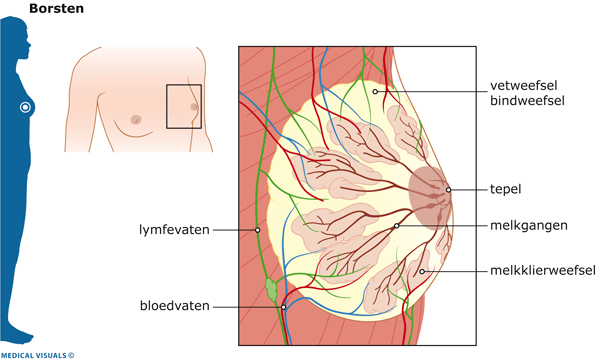

[…] maar gelukkig bleek het een onschuldige cyste (een met vocht gevulde holte). Ik schreef er een blog over en beschreef hoe een mammografie nou in zijn werk […]